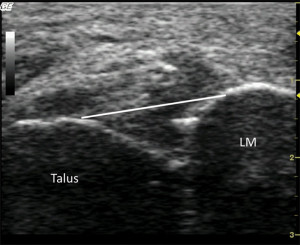

Recent advances in ultrasound imaging and techniques have allowed researchers to use this imaging technique at the ankle. Campbell described dynamic ultrasound imaging as a means of detecting ATFL injury using qualitative appearances of the ligament.28 Mei-Dan et al29 described ultrasound methods combined with ankle motion to quantitatively identify syndesmosis injuries.

More recently, Croy et al30,31 also used ultrasound imaging combined with ankle joint stress tests (stress ultrasonography) to reliably identify laxity changes of the talocrural joint in ankle sprain copers and patients with chronic ankle instability, as well as uninjured controls. ATFL elongation due to anterior drawer and inversion stress was 15% to 25% in CAI patients and significantly greater than uninjured controls. Anterior talar translation of 2.3 mm to 2.8 mm with anterior drawer force was observed in copers and CAI patients, but only 0.2 mm in uninjured controls when translation was measured directly over the origin and insertion of the ATFL. Thus, the increase in talocrural laxity is large in magnitude, but small enough to make it difficult to differentiate from normal talocrural laxity present using manual anterior drawer testing. Further work into the diagnostic accuracy of these methods is ongoing.

Ultrasound affords a real-time evaluation of the site of injury and is tolerated well by patients with both acute and chronic injuries. This type of modality has been described as being “operator dependent,” and unfamiliarity with the capabilities and techniques is one of the main limiting factors precluding its usage in the foot and ankle. Ultrasound is a rapid examination that can be performed inexpensively and does not expose the patient to ionizing radiation as in standard or stress radiographs or during fluoroscopy.

The added benefits of imaging, with and without stress applied, as well as the ability to measure changes between bony landmarks, could potentially help clinicians understand the laxity that results from injury. Moreover, this method allows for bilateral analysis, repeated imaging sessions, and visualization of the ligaments from origin to insertion.25 These characteristics and early positive results in ankle injury patients suggest that the use of ultrasound to determine talocrural movement is promising, but further work must be done to continue to improve upon these methods.